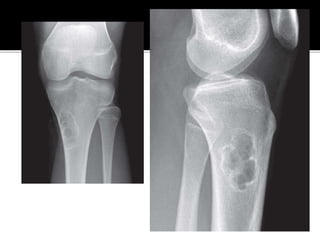

 Imaging - Lobulated areas of stippled

calcification (Popcorn/punctate calcification),

Minimal cortical erosion (except in hand).

 Histology - Benign-appearing hyaline

cartilage.

 Solitary Enchondromas – Observation with

serial radiographs. If stable radiographically,

no further intervention is indicated.

 Symptomatic – Curretage